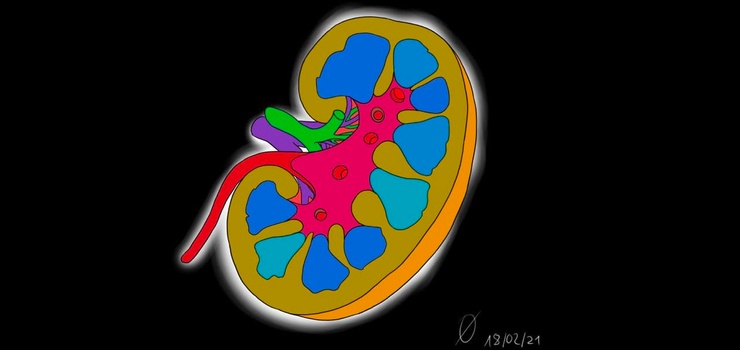

AnatomieA: Urogenitalsystem

Hilft es euch auch, wenn Ihr dringend aufs Klo müsst wenn Ihr euch bewegt!? Let's move together!